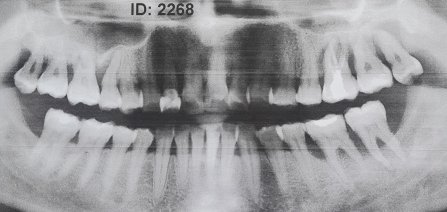

У моего мужа была напухшая щека и болели десна, вскрыли десну поставили дренаж. Вскрыли зуб, удалили нерв. По рентгену ему сказали, что пропадает кость в челюсти. У него начали шататься зубы, три нижних, десна болят, еще говорит, в подбородке что-то болеть стало.

У вашего мужа пародонтоз, лекарства от данного недуга нет. Медицина лишь может замедлить данный процесс. Также регулярная гигиена полости рта, посещение стоматолога, профилактическое лечение может способствовать препятствием для развития данного заболевания. Обратитесь в клинику к стоматологу-пародонтологу и далее следуйте его рекомендациям.